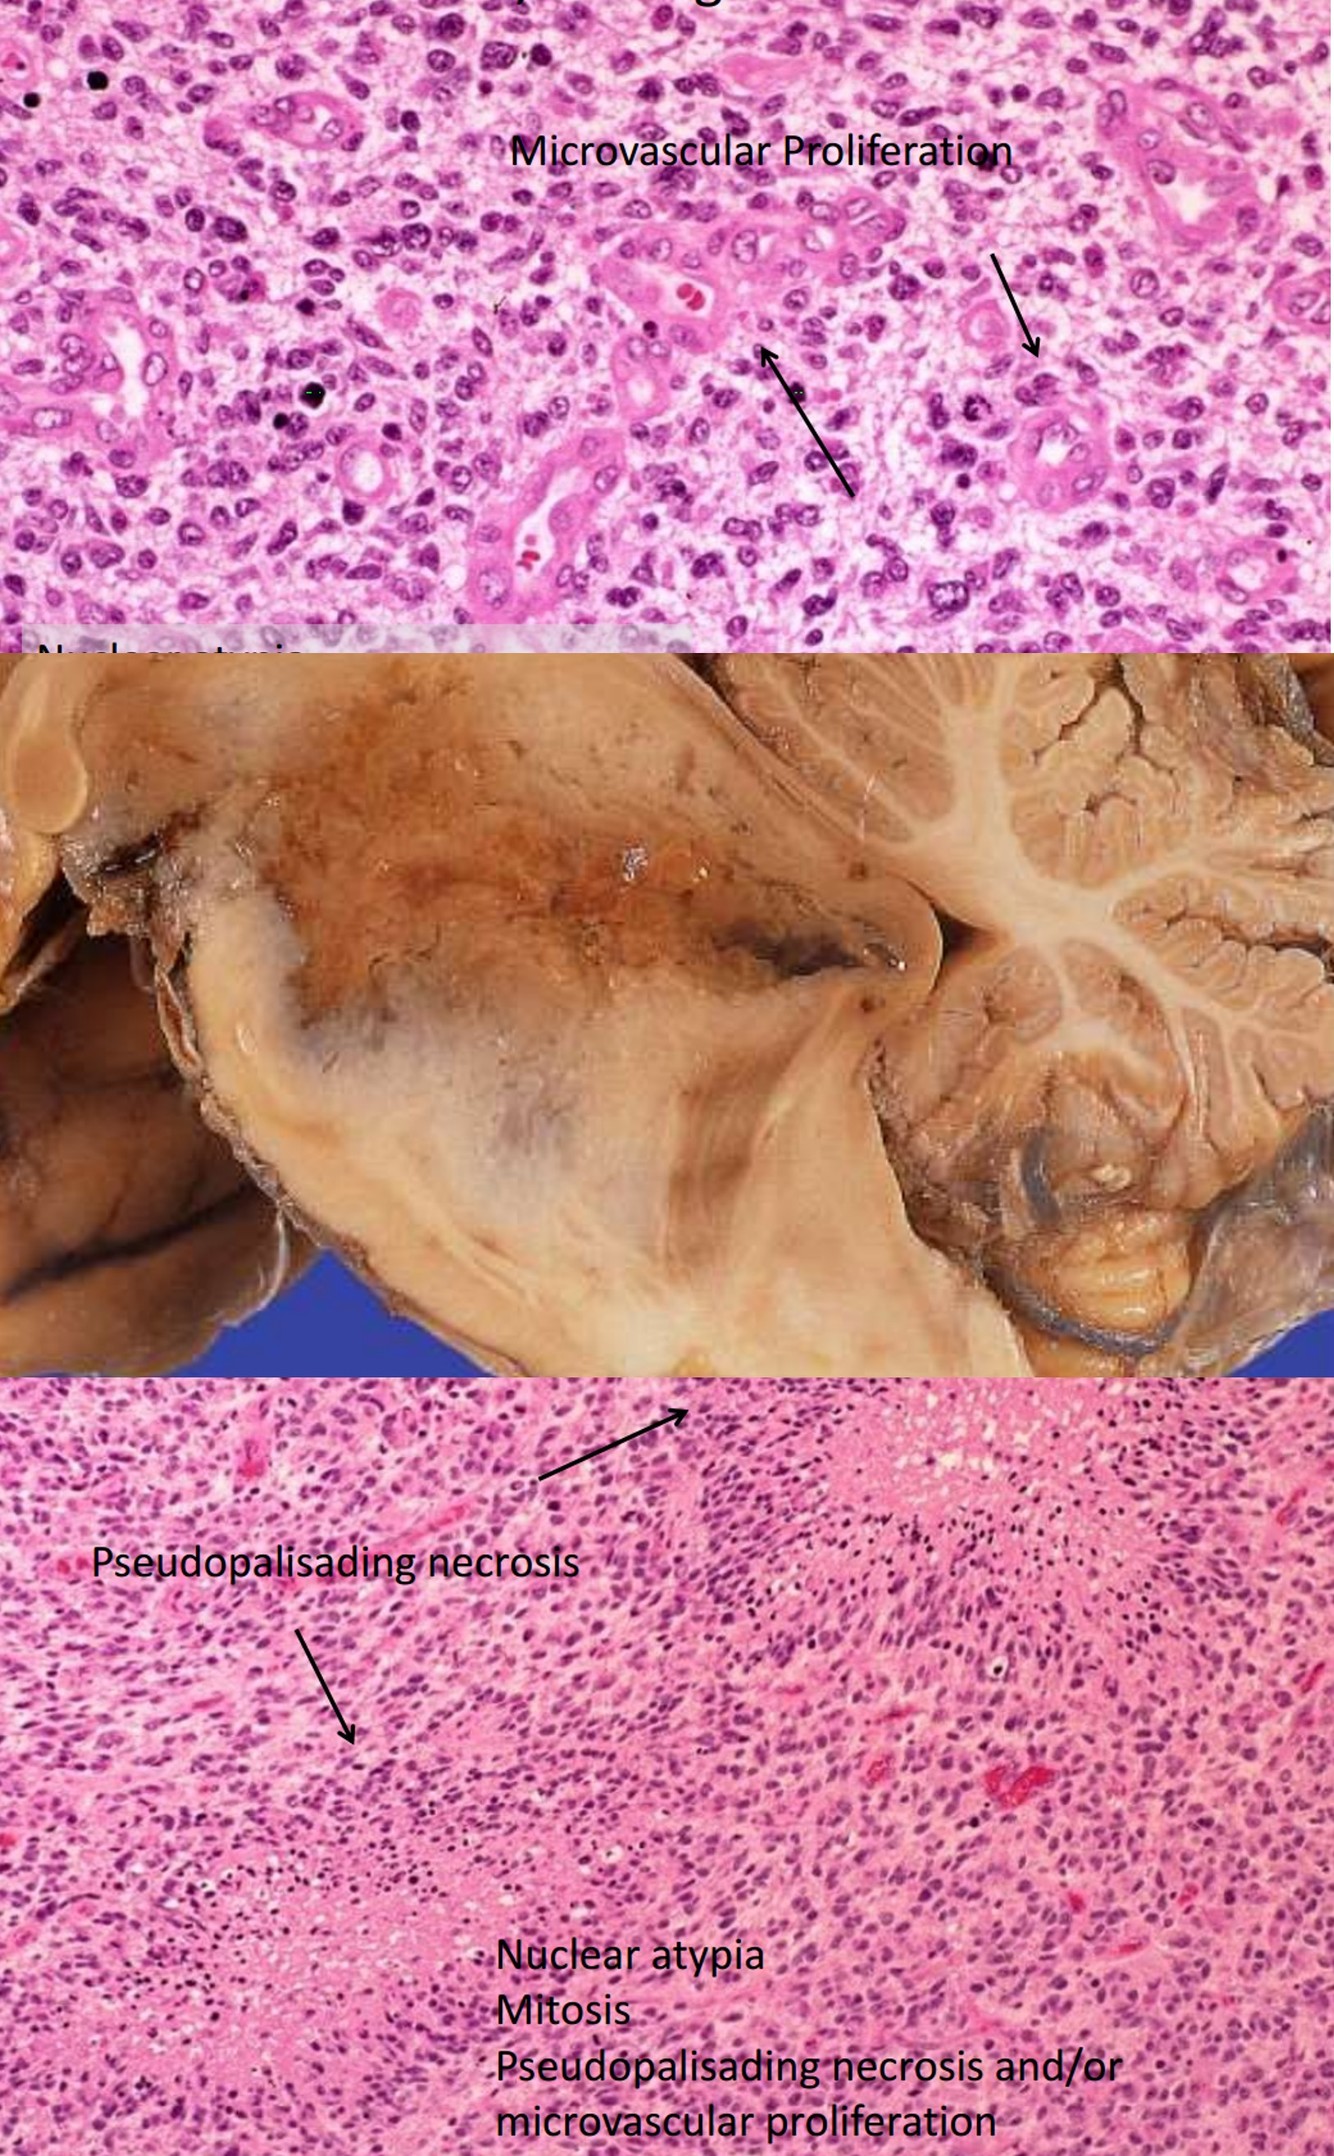

Glioblastoma, WHO grade IV

Astrocytic Genetics

Astrocytic Genetics

- Low Grade: p53 mutations and over expression of PDGF-A and its receptors

- Isocitrate dehydrogenase I (IDH 1), a metabolic enzyme in the citric acid cycle, is commonly mutated in astrocytomas, oligodendroglioma, and mixed gliomas- low grade (II) and anaplastic (III). Associated with better prognosis.

- Primary Glioblastomas: MDM2 amplification, mutated/ aberrant expression of EGFR/p16 deletion/ PTEN mutation

- Better response to chemotherapy: Methylation of promoter for gene encoding MGMT.

- 10q/PTEN deletion (e.g., whole-arm loss): predominantly astrocytic ‘signature’; comprises independent negative prognostic factor

- EGFR amplification (chromosome 7): evident in ‘primary’ glioblastomas (small-cell cytophenotype); comprises independent negative prognostic factor